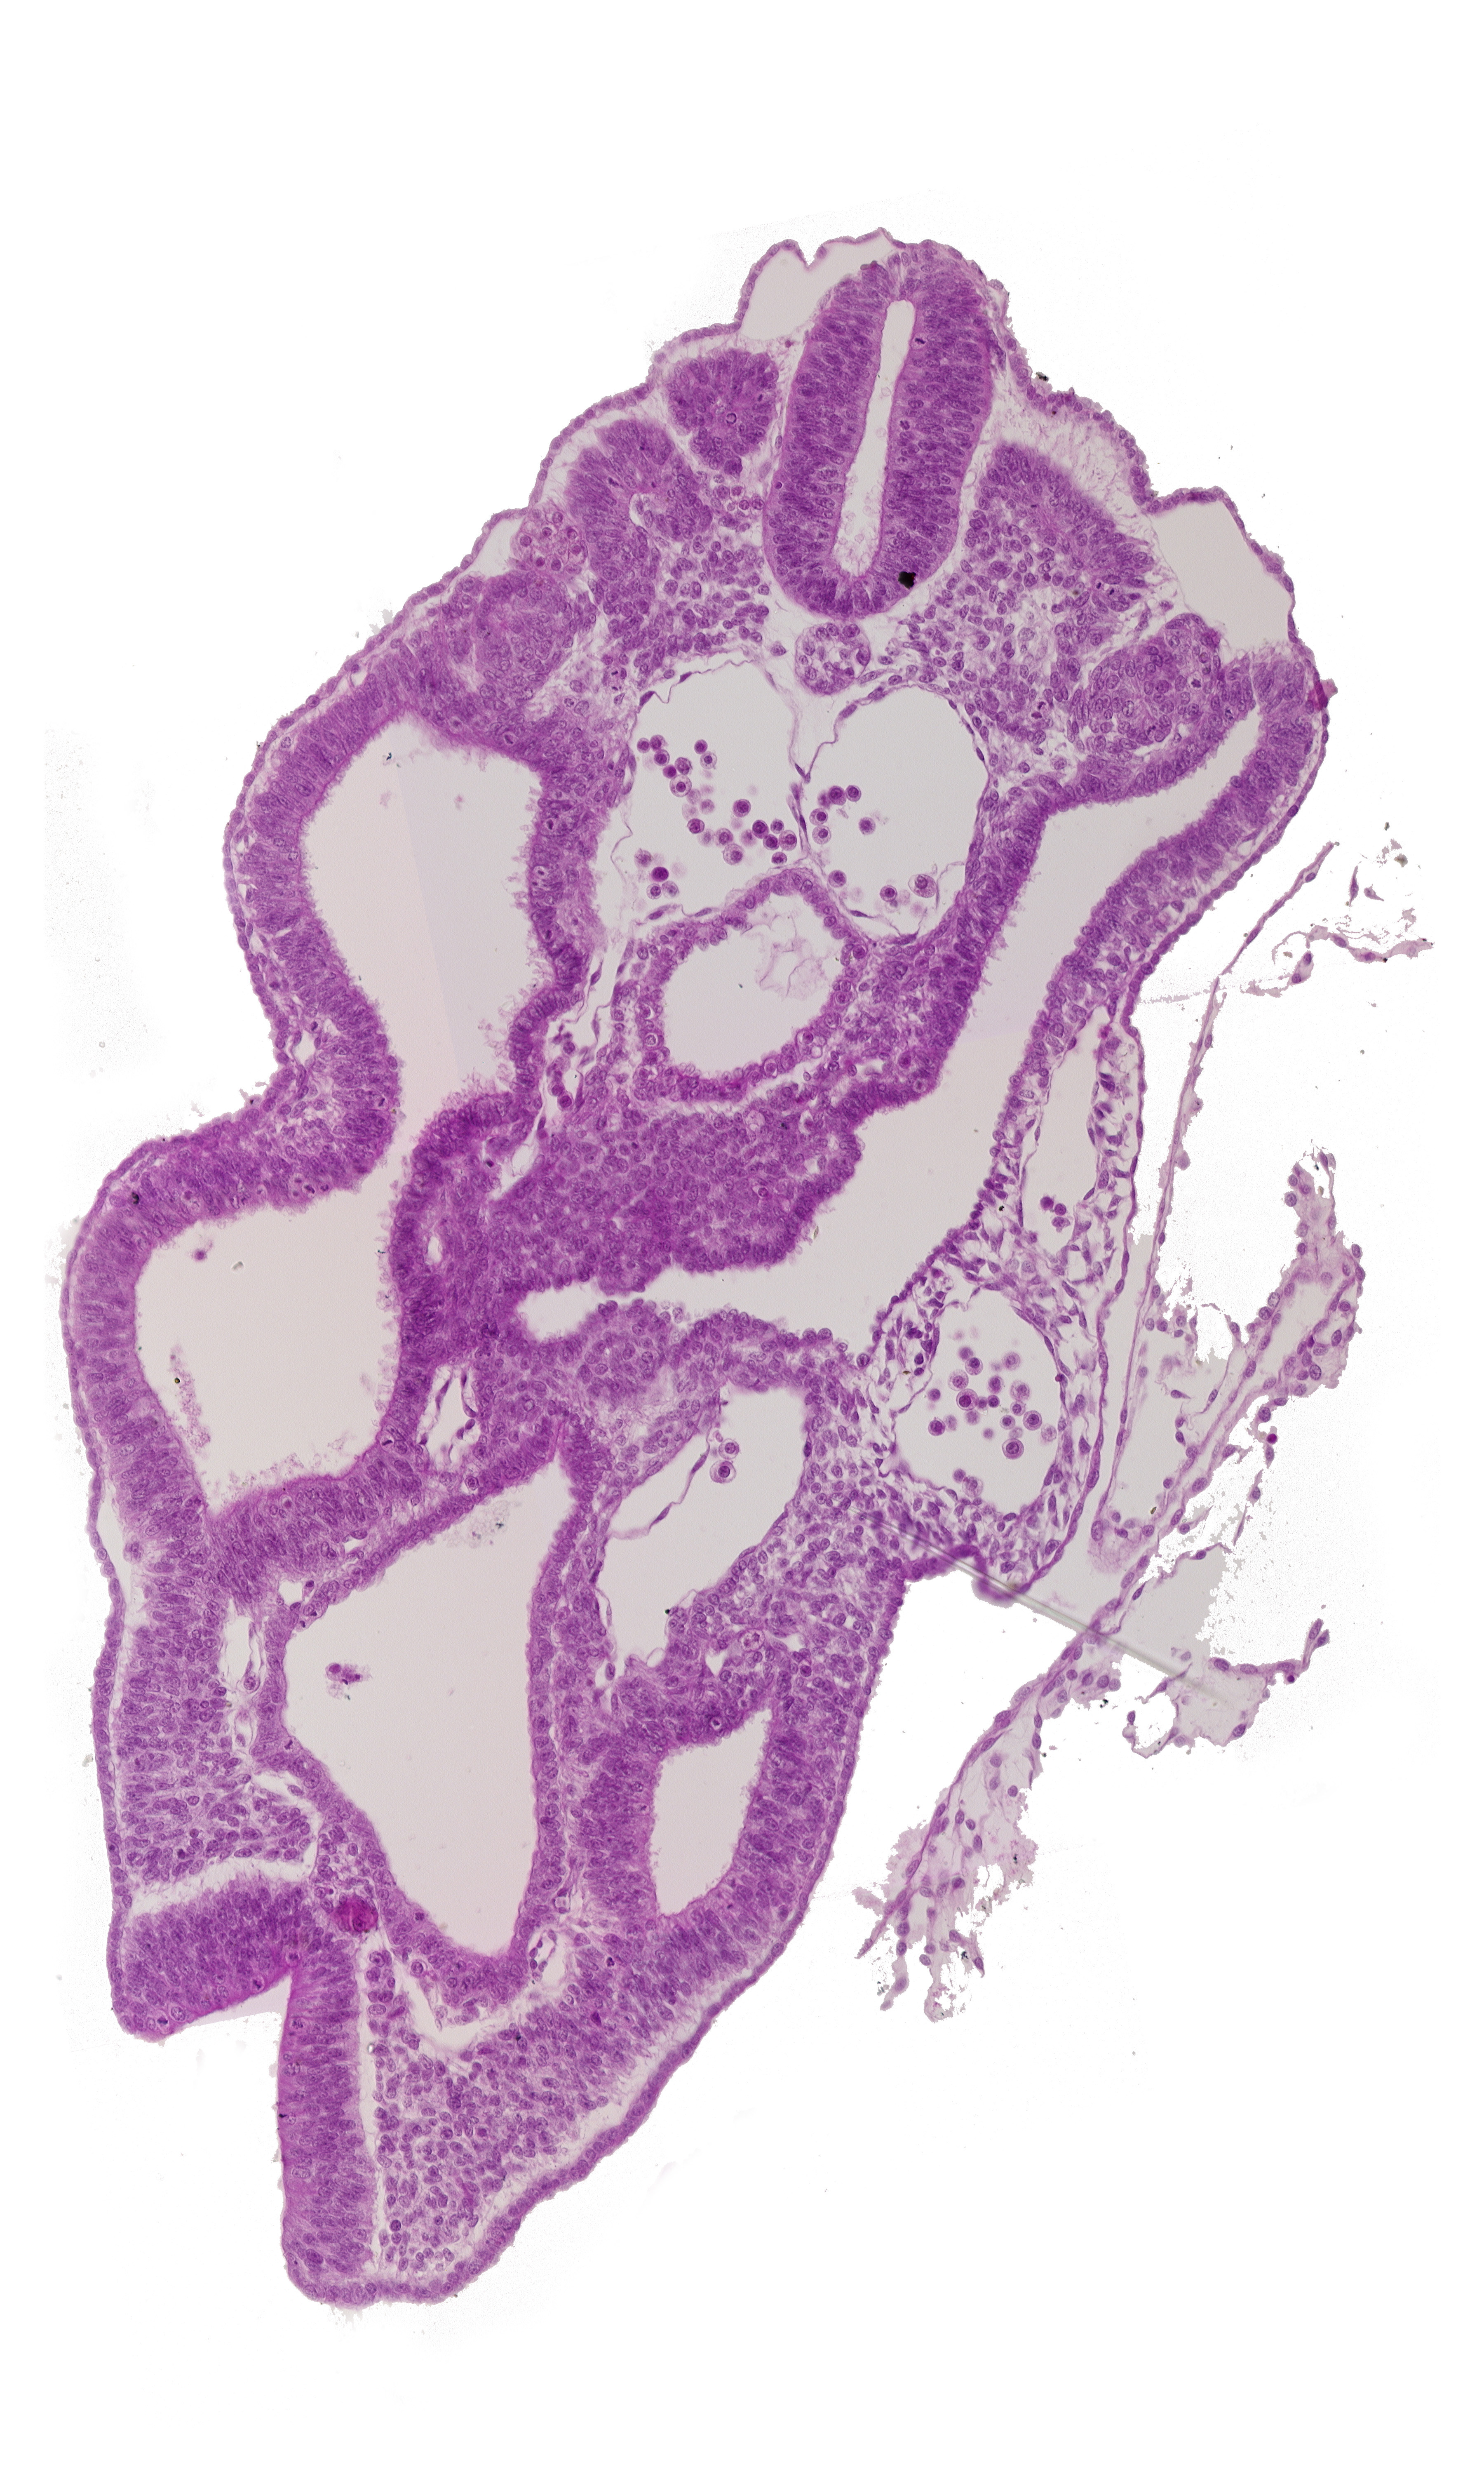

Carnegie Embryo #8943 | Location: 08-02-04

Keywords: cloaca, dermatomyotome 15 (T-3), hindgut, left umbilical artery, left umbilical vein, mesonephric duct, peritoneal cavity

Source: The Virtual Human Embryo.